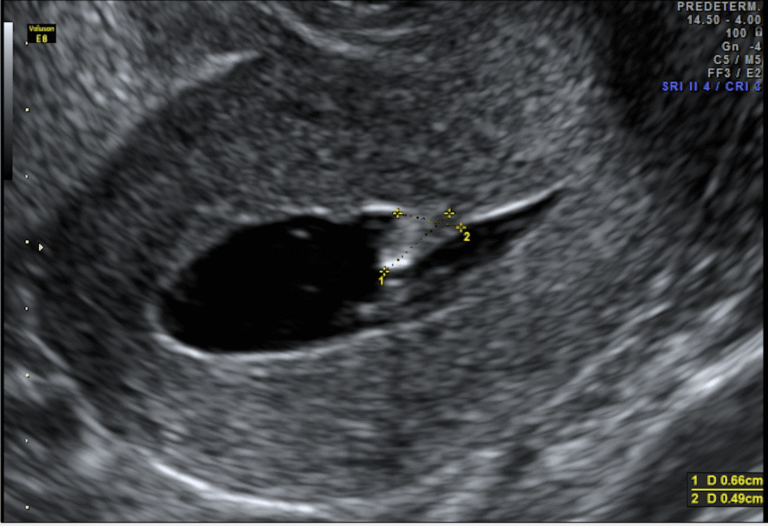

La histerosonografía (también llamada sonohisterografía) es una ecografía transvaginal mejorada que permite visualizar con mayor detalle el interior del útero.

Pólipos endometriales

Miomas submucosos

Sinequias uterinas

Engrosamiento endometrial